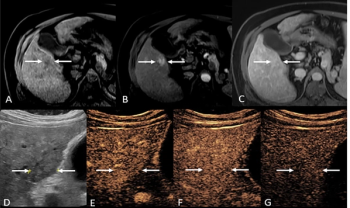

For patients previously assessed with LI-RADS LR-4 and LR-M presentations based on MRI or CT findings, the use of contrast-enhanced ultrasound led to 30 percent of these patients having LR-5 assessments definitive for hepatocellular carcinoma.